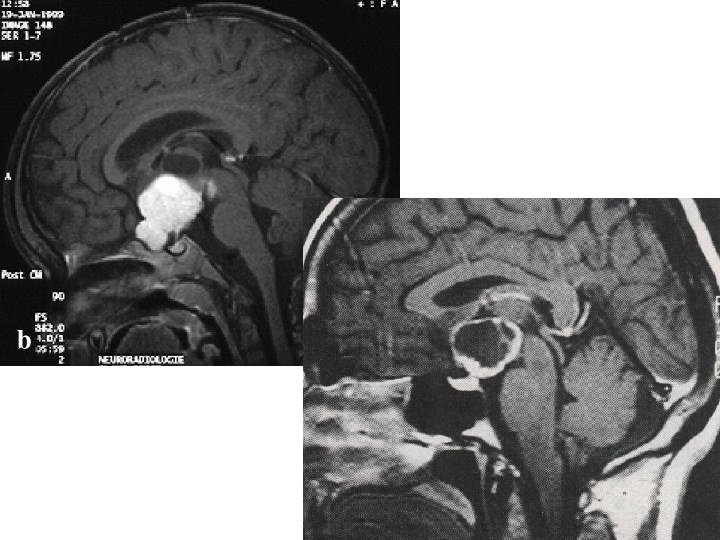

Fall 35 24 Jahre alte Frau. Mit 5 Jahren Exstirpation eines Kraniopharyngeoms; seit dieser Zeit Diabetes insipidus centralis und aggressive Verhaltensstörung. Schwer behinderte Patientin. Langjähriger Diabetes mellitus Typ IIb, Adipositas permagna. Mit 22 Jahren Kolonkarzinom. Aktuell: Computertomografisch Verdacht auf beginnende Leberzirrhose. Transaminasenerhöhung.